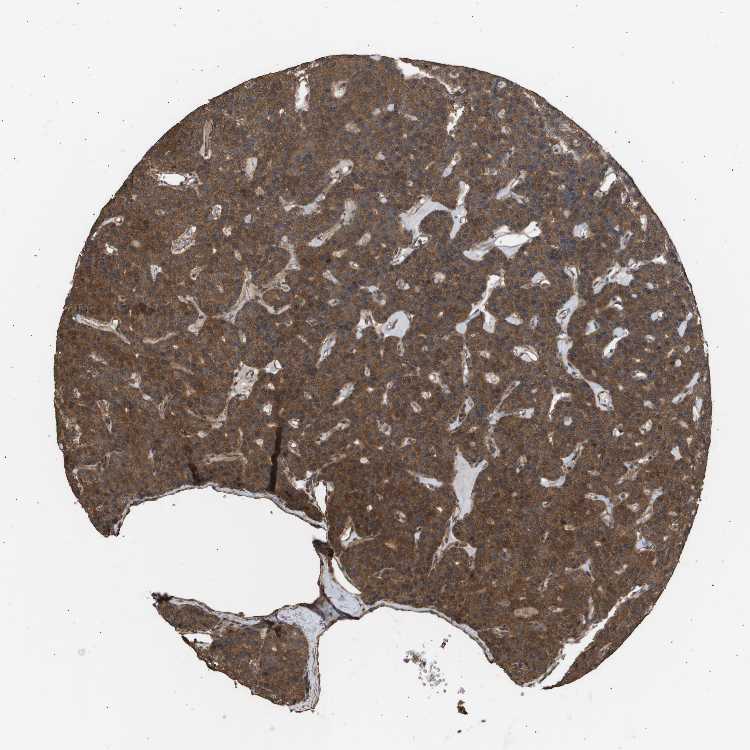

PARATHYROID GLAND - Antibody stainingi

Antibody staining in the annotated cell types in the current human tissue is reported as not detected, low, medium, or high, based on conventional immunohistochemistry profiling in selected tissues. This score is based on the combination of the staining intensity and fraction of stained cells.

Each image is clickable and will lead to virtual microscopy that enables deeper exploration of all samples and also displays staining intensity scores, fraction scores and subcellular localization as well as patient and tissue information for each sample.

Antibody HPA002185Antibody CAB017787

Glandular cells HighHigh